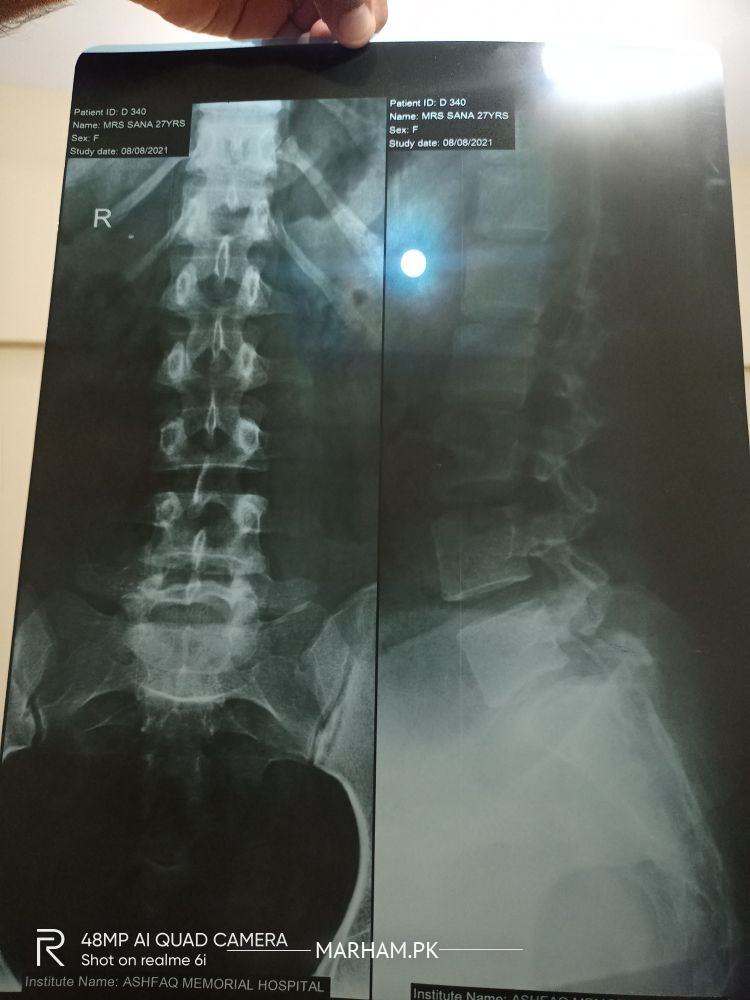

AsalamOalaikum. Dr ye meri xray report hai plz bata den is main kia likha hai or xray sahee hai ya nhi .mjhe lower back pain hai 2 mahine se severe dr ko dikhaya tha unhone 10 days ki med di usse bi koi khas farak nhi para phr ye xray karaya hai .

Disc compression

Need mri of lumbosacral spine screening.

Hi, you have mechanical backache. I suggest you to take pain killers and back care. Thanks

Was. Xray report shows you got spondylolysis at L5 S1

Xrag quality is poor, kindly get yourself checked by an orthopaedic or neurosurgeon, nothing to worry, mean while take rest.

And painkillers

There is a defect in your lower lumbar spine. I need to examine your back before I can advise you any further

A minor break in your spine , which doesn’t need surgery. Work on developing strength in your spinal muscles, avoid bending activities, regular walk or intense activities like jogging, maintain a normal weight. And take some muscle relaxants and anti inflammatory medications.